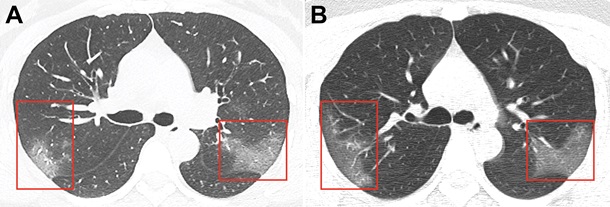

За три дня зона поражения значительно расширилась, показала компьютерная томография.

Снимки были получены в результате компьютерной томографии 33-летней женщины, госпитализированной в китайском городе Ланьчжоу с температурой 39 градусов.

Снимки были сделаны с разницей в три дня. На первом из них в низу легких уже заметны зоны поражения инфекцией — они похожи на большие светлые области. На снимке, сделанном спустя три дня уже заметно, что зона поражения расширяется.

Накануне Daily Mail уже писало об этой пациентке. Тогда тоже отмечалось, что за три дня ее легкие серьезно трансформировались, и это было видно по снимкам рентгена.